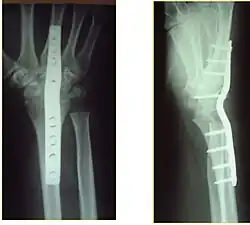

Surgery

Surgery is generally indicated for displaced or unstable fractures.[18] The techniques of surgical management include open reduction internal fixation (ORIF), external fixation, percutaneous pinning, or some combination of the above. The choice of operative treatment is often determined by the type of fracture, which can be categorized broadly into three groups: partial articular fractures, displaced articular fractures, and metaphyseal unstable extra- or minimal articular fractures.[5]

Significant advances have been made in ORIF treatments. Two newer treatments are fragment-specific fixation and fixed-angle volar plating. These attempt fixation rigid enough to allow almost immediate mobility, in an effort to minimize stiffness and improve ultimate function; no improved final outcome from early mobilization (prior to 6 weeks after surgical fixation) has been shown. Although restoration of radiocarpal alignment is thought to be of obvious importance, the exact amount of angulation, shortening, intra-articular gap/step which impact final function are not exactly known. The alignment of the DRUJ is also important, as this can be a source of a pain and loss of rotation after final healing and maximum recovery.

Surgical options have been shown to be successful in patients with unstable extra-articular or minimal articular distal radius fractures. These options include percutaneous pinning, external fixation, and ORIF using plating. Patients with low functional demand of their wrists can be treated successfully with nonsurgical management; however, in more active and fit patients with fractures that are reducible by closed means, nonbridging external fixation is preferred, as it has less serious complications when compared to other surgical options.[5] The most common complication associated with nonbridging external fixation is pin tract infection, which can be managed with antibiotics and frequent dressing changes, and rarely results in reoperation.[5] The external fixator is placed for 5 to 6 weeks and can be removed in an outpatient setting.[5]

If the fractures are unlikely to be reduced by closed means, open reduction with internal plate fixation is preferred.[5] Although major complications (i.e. tendon injury, fracture collapse, or malunion) result in higher reoperation rates (36.5%) compared to external fixation (6%), ORIF is preferred, as this provides better stability and restoration of the volar tilt.[5][23] Following the operation, a removable splint is placed for 2 weeks, during which time patients should mobilize the wrist as tolerated.[5]